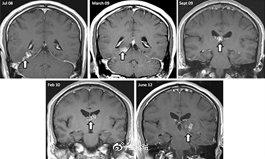

其损害主要表现为急性广泛的出血性坏死性脑膜脑炎,在脑脊液和病灶组织中有大量滋养体。宿主的易感因素可能存在缺乏IgA,因而粘膜的防御功能受到削弱所致。棘阿米巴的分布更广泛,在呼吸道分泌物中常可发现。病变原发部位在皮肤或眼、肺、胃、肠和耳等引起炎症和肉芽肿,在宿主免疫抑制或减弱情况下,可能经血源传播到中枢神经系统而引起肉芽肿性阿米巴脑炎(GAE)。其损害多为慢性肉芽肿性病变;因此病程较长,可达18-120天。有少数病程呈急性,在10~14天内死亡。

除此之外神经系统体征显示局灶性单侧损害,有严重的局灶性坏死和水肿。病人头痛、发热呕吐、颈强直、眩晕、嗜睡、精神错乱、共济失调直至昏迷和死亡。棘阿米巴未转移至脑的一般不致命,少数可自愈。如果一旦转移至脑,感染者一般在出现症状后的1至18天内死亡。